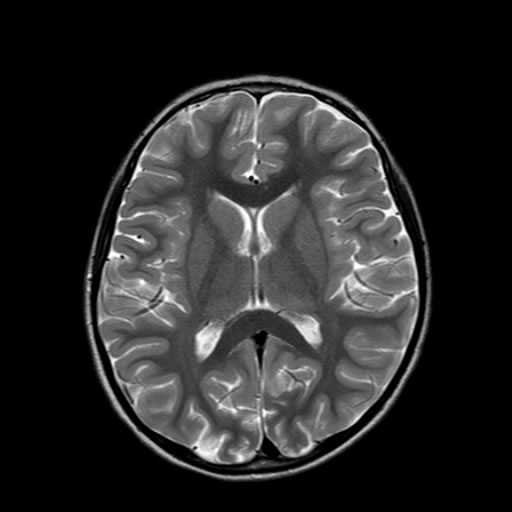

Niña de 5 años de edad, debut de crisis convulsiva.